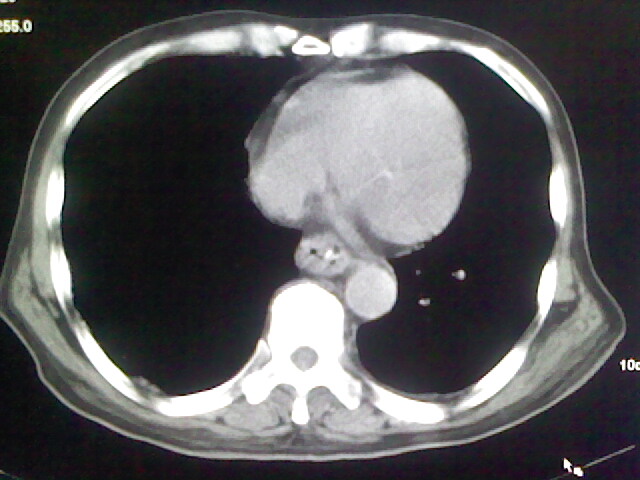

男,70岁,脑出血,长期卧床,左侧背部可触及肿块

肺部感染,背部筋膜增厚,考虑坠积性水肿或炎症

右侧肺部见片状密度增高影,边缘模糊。考虑炎症。另食管壁增厚。

食道里是什么

你放上去的